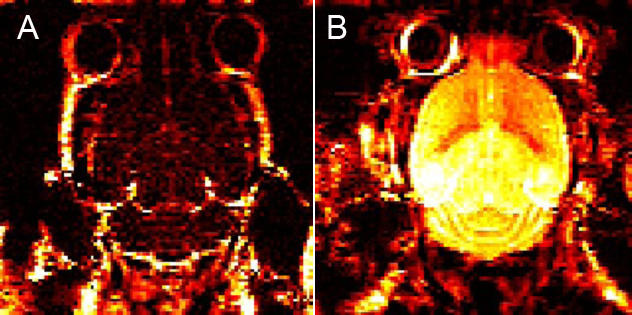

We investigated the ability of a synthetic peptide to permeabilize the BBB for improved treatment with targeted therapies preclinically. Dynamic contrast enhanced MRI (DCE-MRI) was carried out on nod/scid mice to study the therapeutic window of peptide-mediated BBB permeabilization. Further, both in vivo and in vitro assays were used to determine peptide toxicity and to obtain mechanistic insight into its action on the BBB. The therapeutic impact of the peptide on metastases was evaluated combined with the mitogen-activated protein kinase pathway inhibitor dabrafenib, targeting BRAF mutated melanoma cells, which is otherwise known not to cross the intact BBB.

Our results from the DCE-MRI experiments showed effective peptide-mediated BBB permeabilization lasting for up to 1 hour. Mechanistic studies showed a dose-dependent effect of the peptide caused by induction of endocytosis. Combined treatment with the peptide and dabrafenib reduced the brain metastatic burden in mice and increased animal survival, and PET/CT showed that the peptide also facilitated the delivery of compounds with molecular weights as large as 150 kDa into the brain.